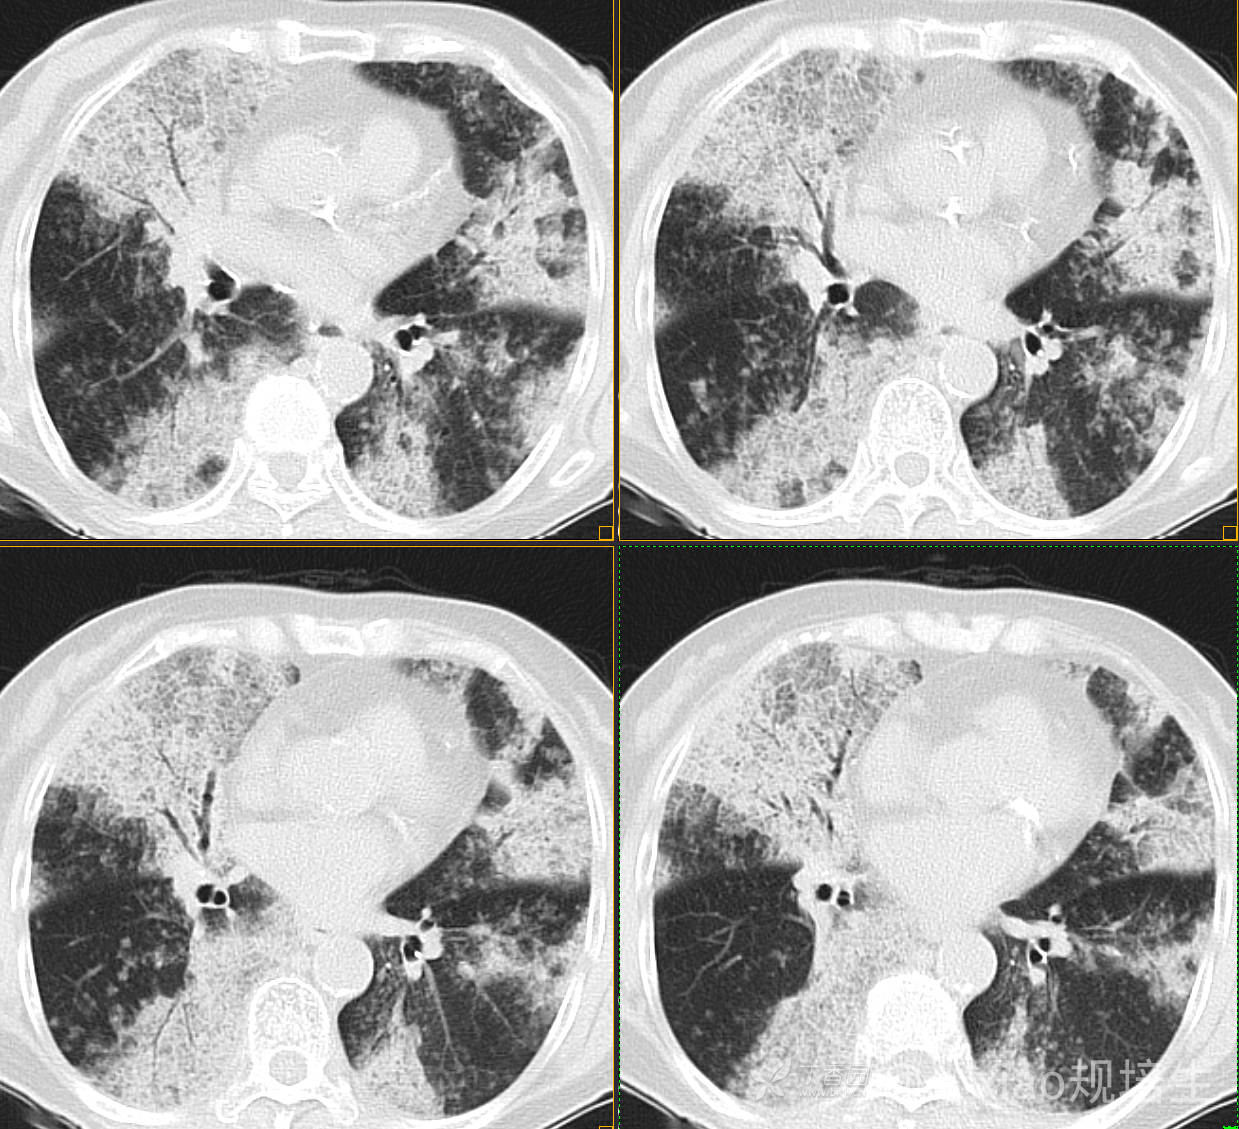

患者,女,89岁

咳嗽,咳痰一月余

肺泡蛋白沉着病 (19)

腺癌 (183)

弥漫性囊性肺病 (9)